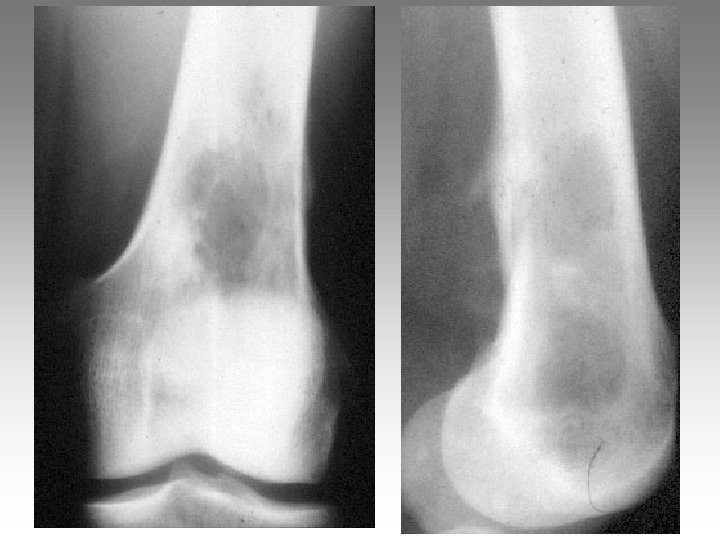

Hanche, T. , fract. fatigue Tendinites bursites, radic. Genou douloureux non traumatique Sémiologie Ponction +++ mécanique inflammatoire Rx inflammation Rx N Rx a. N < 40 ans interligne pincé Arthrose FT - FP contexte +++ > 40 ans Biologie, BS, Rx, IRM, écho interligne normal IRM AND, FF Paget, HOV ONA, OAN OAPH Ostéochond. infection IRM Arthroscopie Scinti. Os. LC Ménisque Coagul. PR, RP, Still, LED, SA…. Goutte, CCA AND ONA Ostéochondrite Pyogène, BK, Gono. , autres Hydarthrose X? Ostéochondromatose Synonite VN, T. , coag.

Genou douloureux non traumatique Sémiologie Ponction +++ mécanique inflammatoire Rx inflammation Rx N Rx a. N < 40 ans interligne pincé Arthrose FT - FP contexte +++ > 40 ans Biologie, BS, Rx, IRM, écho interligne normal IRM AND, FF Paget, HOV ONA, OAN OAPH Ostéochond. infection IRM Arthroscopie Scinti. Os. LC Ménisque Coagul. PR, RP, Still, LED, SA…. Goutte, CCA AND ONA Ostéochondrite Pyogène, BK, Gono. , autres Hydarthrose X? Ostéochondromatose Synonite VN, T. , coag.

Genou douloureux non traumatique Sémiologie Ponction +++ mécanique inflammatoire Rx inflammation Rx N Rx a. N < 40 ans interligne pincé Arthrose FT - FP contexte +++ > 40 ans interligne normal IRM AND, FF Paget, HOV ONA, OAN OAPH infection Biologie, BS, Rx, IRM, écho IRM Arthroscopie Scinti. Os. LC Ménisque Coagul. PR, RP, Still, LED, SA…. Goutte, CCA AND ONA Banal, BK, Gono. , autres Hydarthrose X? Ostéochondromatose Synonite VN, T. osseuse